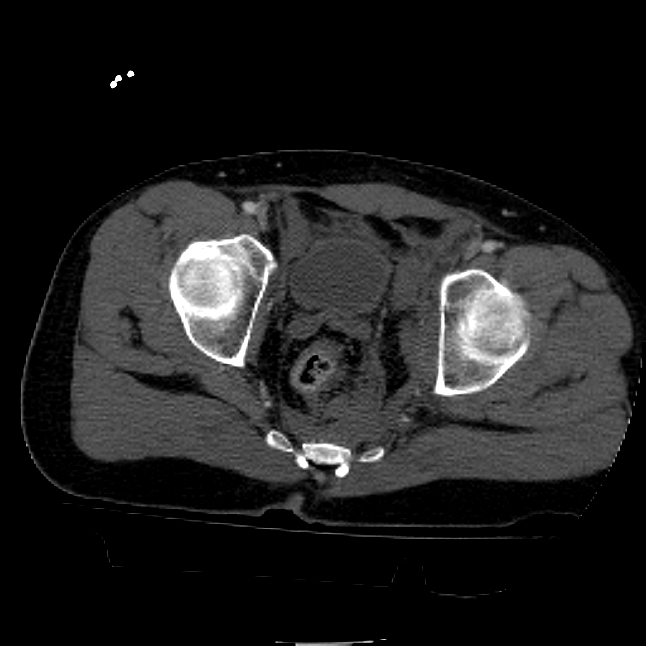

25 yo brittle diabetic, became hypoglycemic and passed out on his motorcycle. Sustained bilateral lateral Hoffa fractures with associated LCL injury on the right and right distal radius fracture. I have questions regarding his pelvic ring/acetabular fracture on the left. Appears to be a very low posterior column fracture with associated posterior wall, marginal impaction. Superior and inferior rami fractures as well on the left giving him a floating segment of inf ramus/ischium/posterior column, but no detectable posterior ring injury. Should the posterior column/posterior wall fracture be addressed surgically because of the marginal impaction? Or is this fracture low enough to be treated non-operatively? I appreciate the input.

It's an interesting case. The plain films show the impaction, but most of the joint looks pretty good. The CT cuts look awful, though.

The impaction is so big I don't think I would ignore it. It IS down low, but it takes up almost the whole southern hemisphere of his joint.

interesting case. I believe a common mistake is saying that the dome is ok so I can treat this nonoperatively. This only works for tr and t type fractures not posterior column posterior wall fractures. Matta's results show no difference with impaction. Mine show worse results with impaction but still better results than nonoperatively. The really bad ones are the elderly with dome impaction but I ve been surprised by a few of those as well. This I more posterior and I think will do well with good fixation. This means a good reefing behind the piece (?2.7mm or 2.0mm to get more screws) to prevent the late collapse. I also am very gingerly with their post op tdwb x 3 months with no pt to that extremity. Hope this helps.